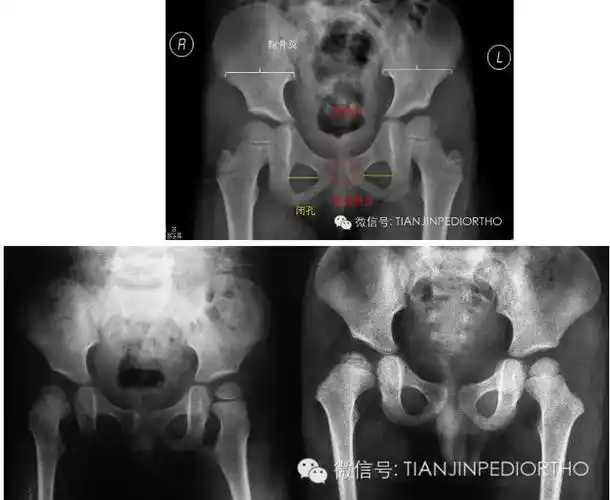

儿童股骨头坏死---标准骨盆正位,双髋蛙位片的问与答 - 好大夫在线